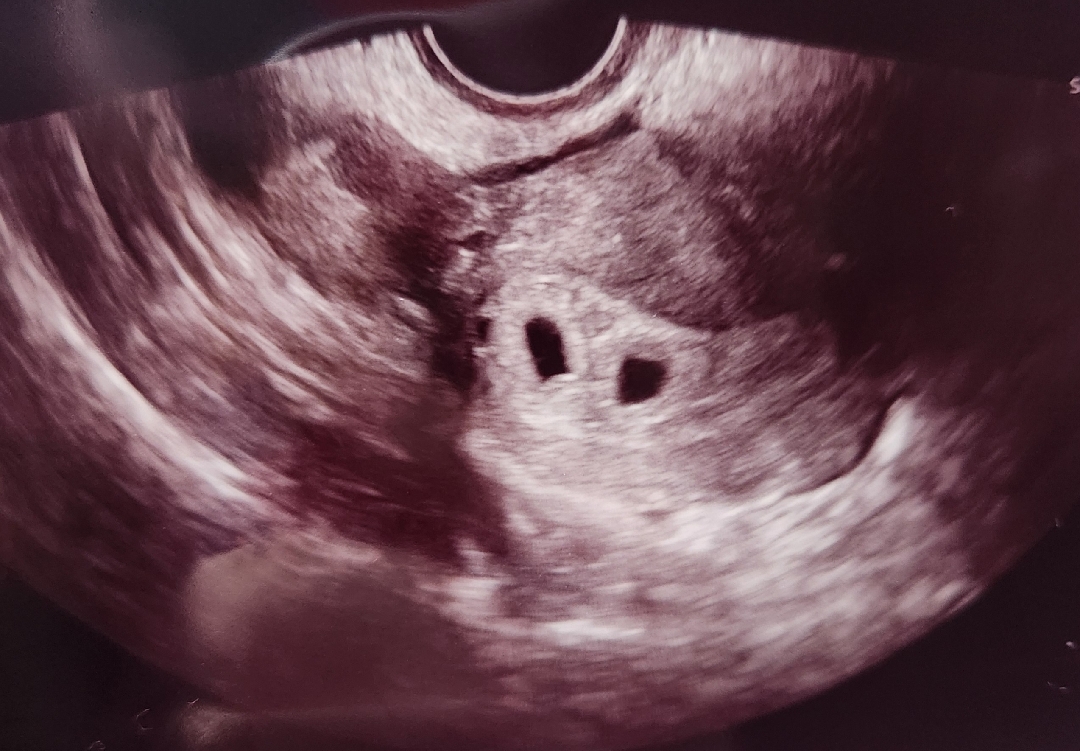

5주차 첫 초음파

오늘 정확히 5주차 되는 날 초음파 사진 확인하고 둥이인걸 알게 되었어요ㅎㅎ 놀라서 선생님한테 물어보고 싶은것도 다 못 물어보고 나와버렸네요ㅜㅜ 이제야 사진을 자세히 보고있는데 아기집 크기는 괜찮은지 난황까지 보일줄 알았는데 없는게 마음에 걸리네요ㅜㅜ아직 이른거겠죠??

저도 오늘 초음파 보고 아기집 두개 봤어요! 정확히 5주 0일이고 아기집만 보이는게 정상이래요 다태아로 임신확인서 받아왔고 다음주에 진료보러 가요~~ 저는 아기집 크기 0.52cm,0.47cm 이였어요!